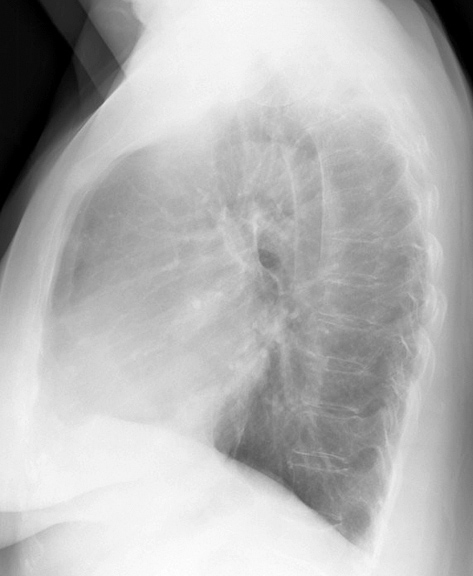

Gallery Cardiac Mitral Valve Disease Mitral Valve Disease Case 9 Lat

Mitral Valve Disease

Case 9 Lat